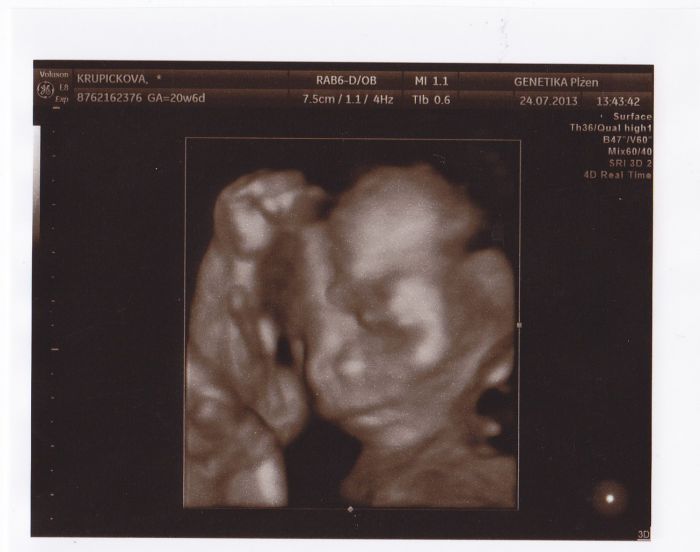

dobre ranko,tak vcera na screeningu super,vse je v poradku moc se nevrtel byl v klubicku ale to nevadi na tom 3D si ho natoci jak chteji.jsme strasne stastny.je potvrzenej Petricek.vcera mel 380g a 26cm az k pate.byly jsme 20+6 a odpovidal 20+4.vybavicku postupne kupuju ale jeste neperu.v cem to perete vy?v nejakym specialnim prasku opro prtata?vanoce jsme letos pro rodiny zrusily.zadny darky zadny navstevy.budeme radi kdyz to tak zvladneme financne a kdyz budu v sestinedeli myslim ze budu mit dost starosti s malym a vubec se vsechno naucit.no jo vypleskla prvorodicka....jinak u nas porad dusno ani kapka.nemuzu vubec spat.dneska uz od tri.ale kdyz mam vychazky to bych spala

pohladte ty nase poklady.pa

Super fotečka

Katko, fotka je moc pěkná:-) u dcery před 12 lety jsem to prala normálně všechno dohromady, mikdy jsem tyhle věci neřešila a je to zdravá holka, budu to te´d dělat stejně. podle mě je hlavní, aby se to pro miminko žehlilo, ať se spálí případné bakterie, a to stačí tak ty první 3 měsíce, jinak si myslím, že to je taky fuk. Vůbec si myslím, že ty děti vydřží víc než si myslíme :-)